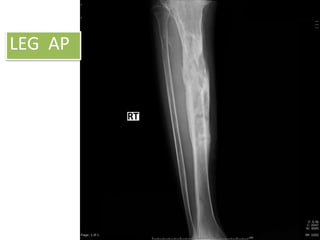

LEG AP

LEG LAT